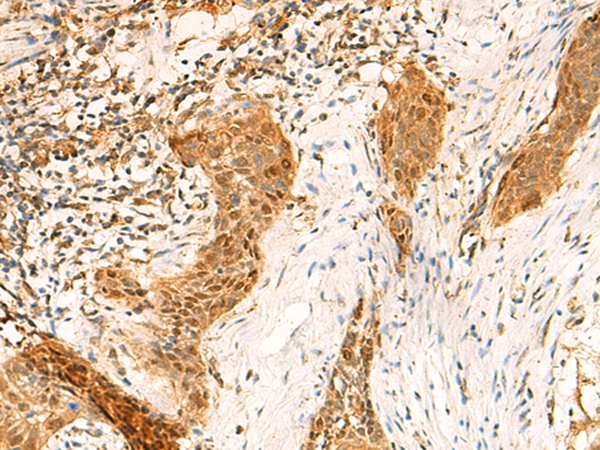

IHC positive control: |

Human esophagus cancer |

IHC Recommend dilution: |

50-300 |